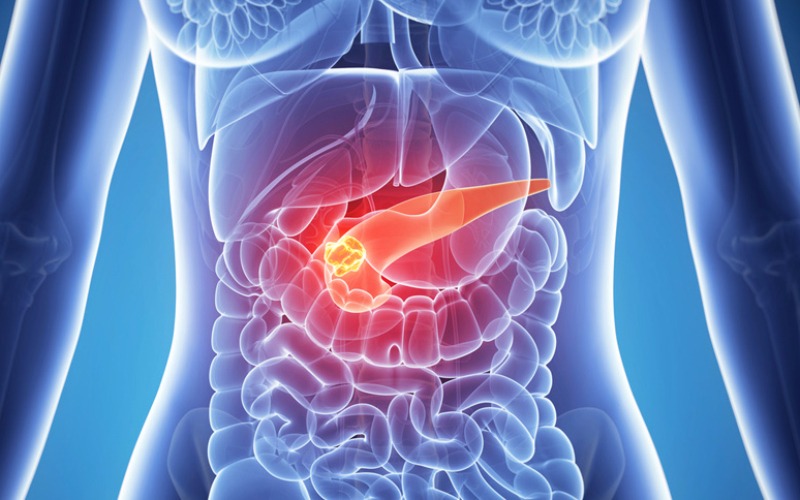

Diabetes memiliki mekanisme yang bekerja pada 4 organ tubuh. Organ tersebut yaitu : hepar (hati), Pankreas, sistem pencernaan, dan sel-sel tubuh.

Pankreas

Pankreas merupakan organ yang berfungsi menghasilkan hormon insulin. Dimana insulin sendriri merupakan “kendaraan” yang membawa oksigen dan gula untuk masuk ke dalam sel-sel tubuh.

Pada penderita diabetes, pankreas tidak dapat bekerja secara baik. Produksi hormon insulin oleh pankreas tidak memenuhi kebutuhan tubuh. Atau bisa juga pankreas tidak dapat memproduksi hormon insulin sama sekali. Hal ini menyebabkan kadar gula dalam darah meningkat karena gula dalam darah tidak dapat diserap oleh sel-sel atau organ tubuh.